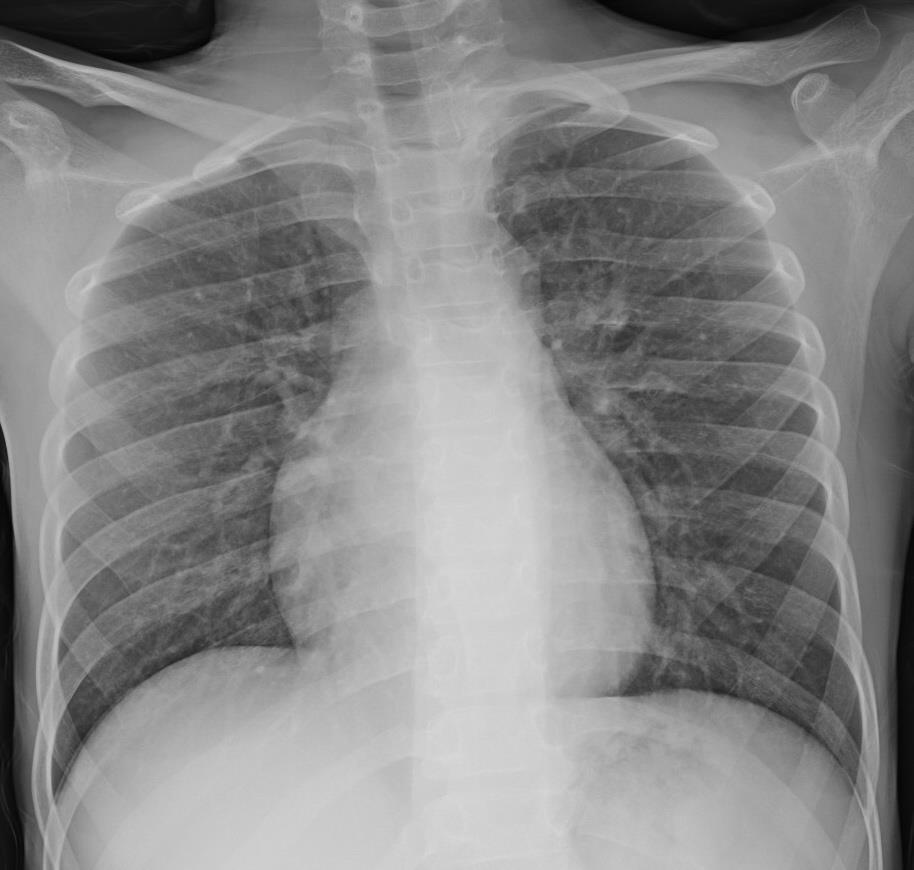

Acute Pediatric COVID-19: CT

21 Imaging of Covid 19 infection in children

3 Phases

Early: "Halo" sign

Local infection

Progressive: Diffuse GGO

Developed: Consolidation

Surr vasc congestion

Inflammation - adj alveoli

Alveoli fill with fluid/cells

Lung Disorders CXR

COVID 19

• Patchy bilateral GGO, Consolidations or both

• Peripheral and lower lung zone predominance